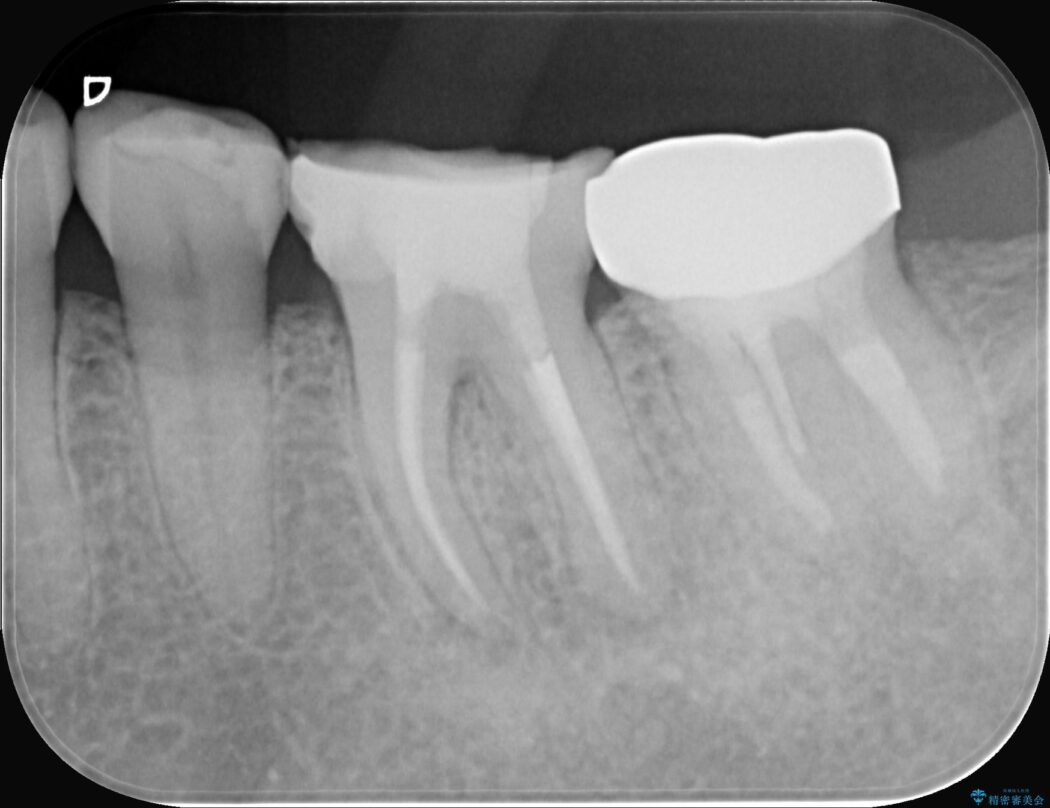

レントゲンを確認すると、歯髄腔が狭くなり根管が石灰化している難症例でした。

患者様の大切な歯を残すため、歯科用顕微鏡を用いた精密根管治療を行うことで、狭く、見えにくい根管を正確に探し出し、治療を完了させる計画を立案しました。

今回の治療は、特に難易度の高い石灰化した根管が対象でした。

まず、治療中の細菌感染を防ぐためにラバーダムを使用。次に、歯科用顕微鏡で治療部位を何十倍にも拡大しながら、狭窄した根管の入り口を探し、慎重に拡大・清掃を行いました。顕微鏡を用いることで、肉眼では不可能だった根管内部の細かい構造を確認しながら、感染源を徹底的に除去することができました。これにより、難症例の奥歯でも再発リスクを抑えた適切な処置を行うことができ、治療後に痛みは解消。大切な歯を長期間にわたり保存することができました。